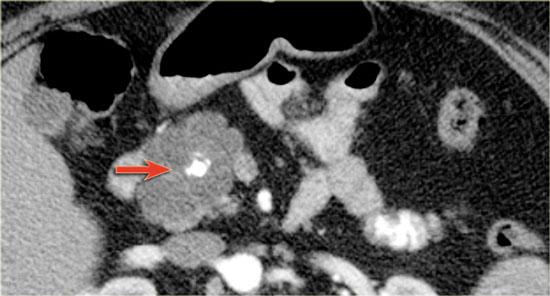

Hình ảnh CT của một IPMN với ống tụy giãn (mũi tên xanh).

Lưu ý nốt đặc có ngấm thuốc tại đầu tụy (mũi tên đỏ).

Tiếp tục xem hình ảnh siêu âm.

Hình ảnh siêu âm cho thấy thành phần ống nhánh kích thước lớn nằm trong đầu tụy.